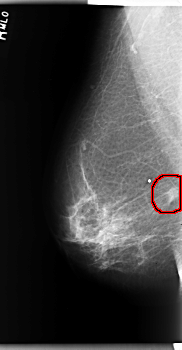

C_0202_1.RIGHT_MLO

FILE: C_0202_1.RIGHT_MLO.OVERLAY

TOTAL_ABNORMALITIES 1

ABNORMALITY 1

LESION_TYPE MASS SHAPE IRREGULAR MARGINS SPICULATED

ASSESSMENT 5

SUBTLETY 5

PATHOLOGY MALIGNANT

TOTAL_OUTLINES 1

BOUNDARY